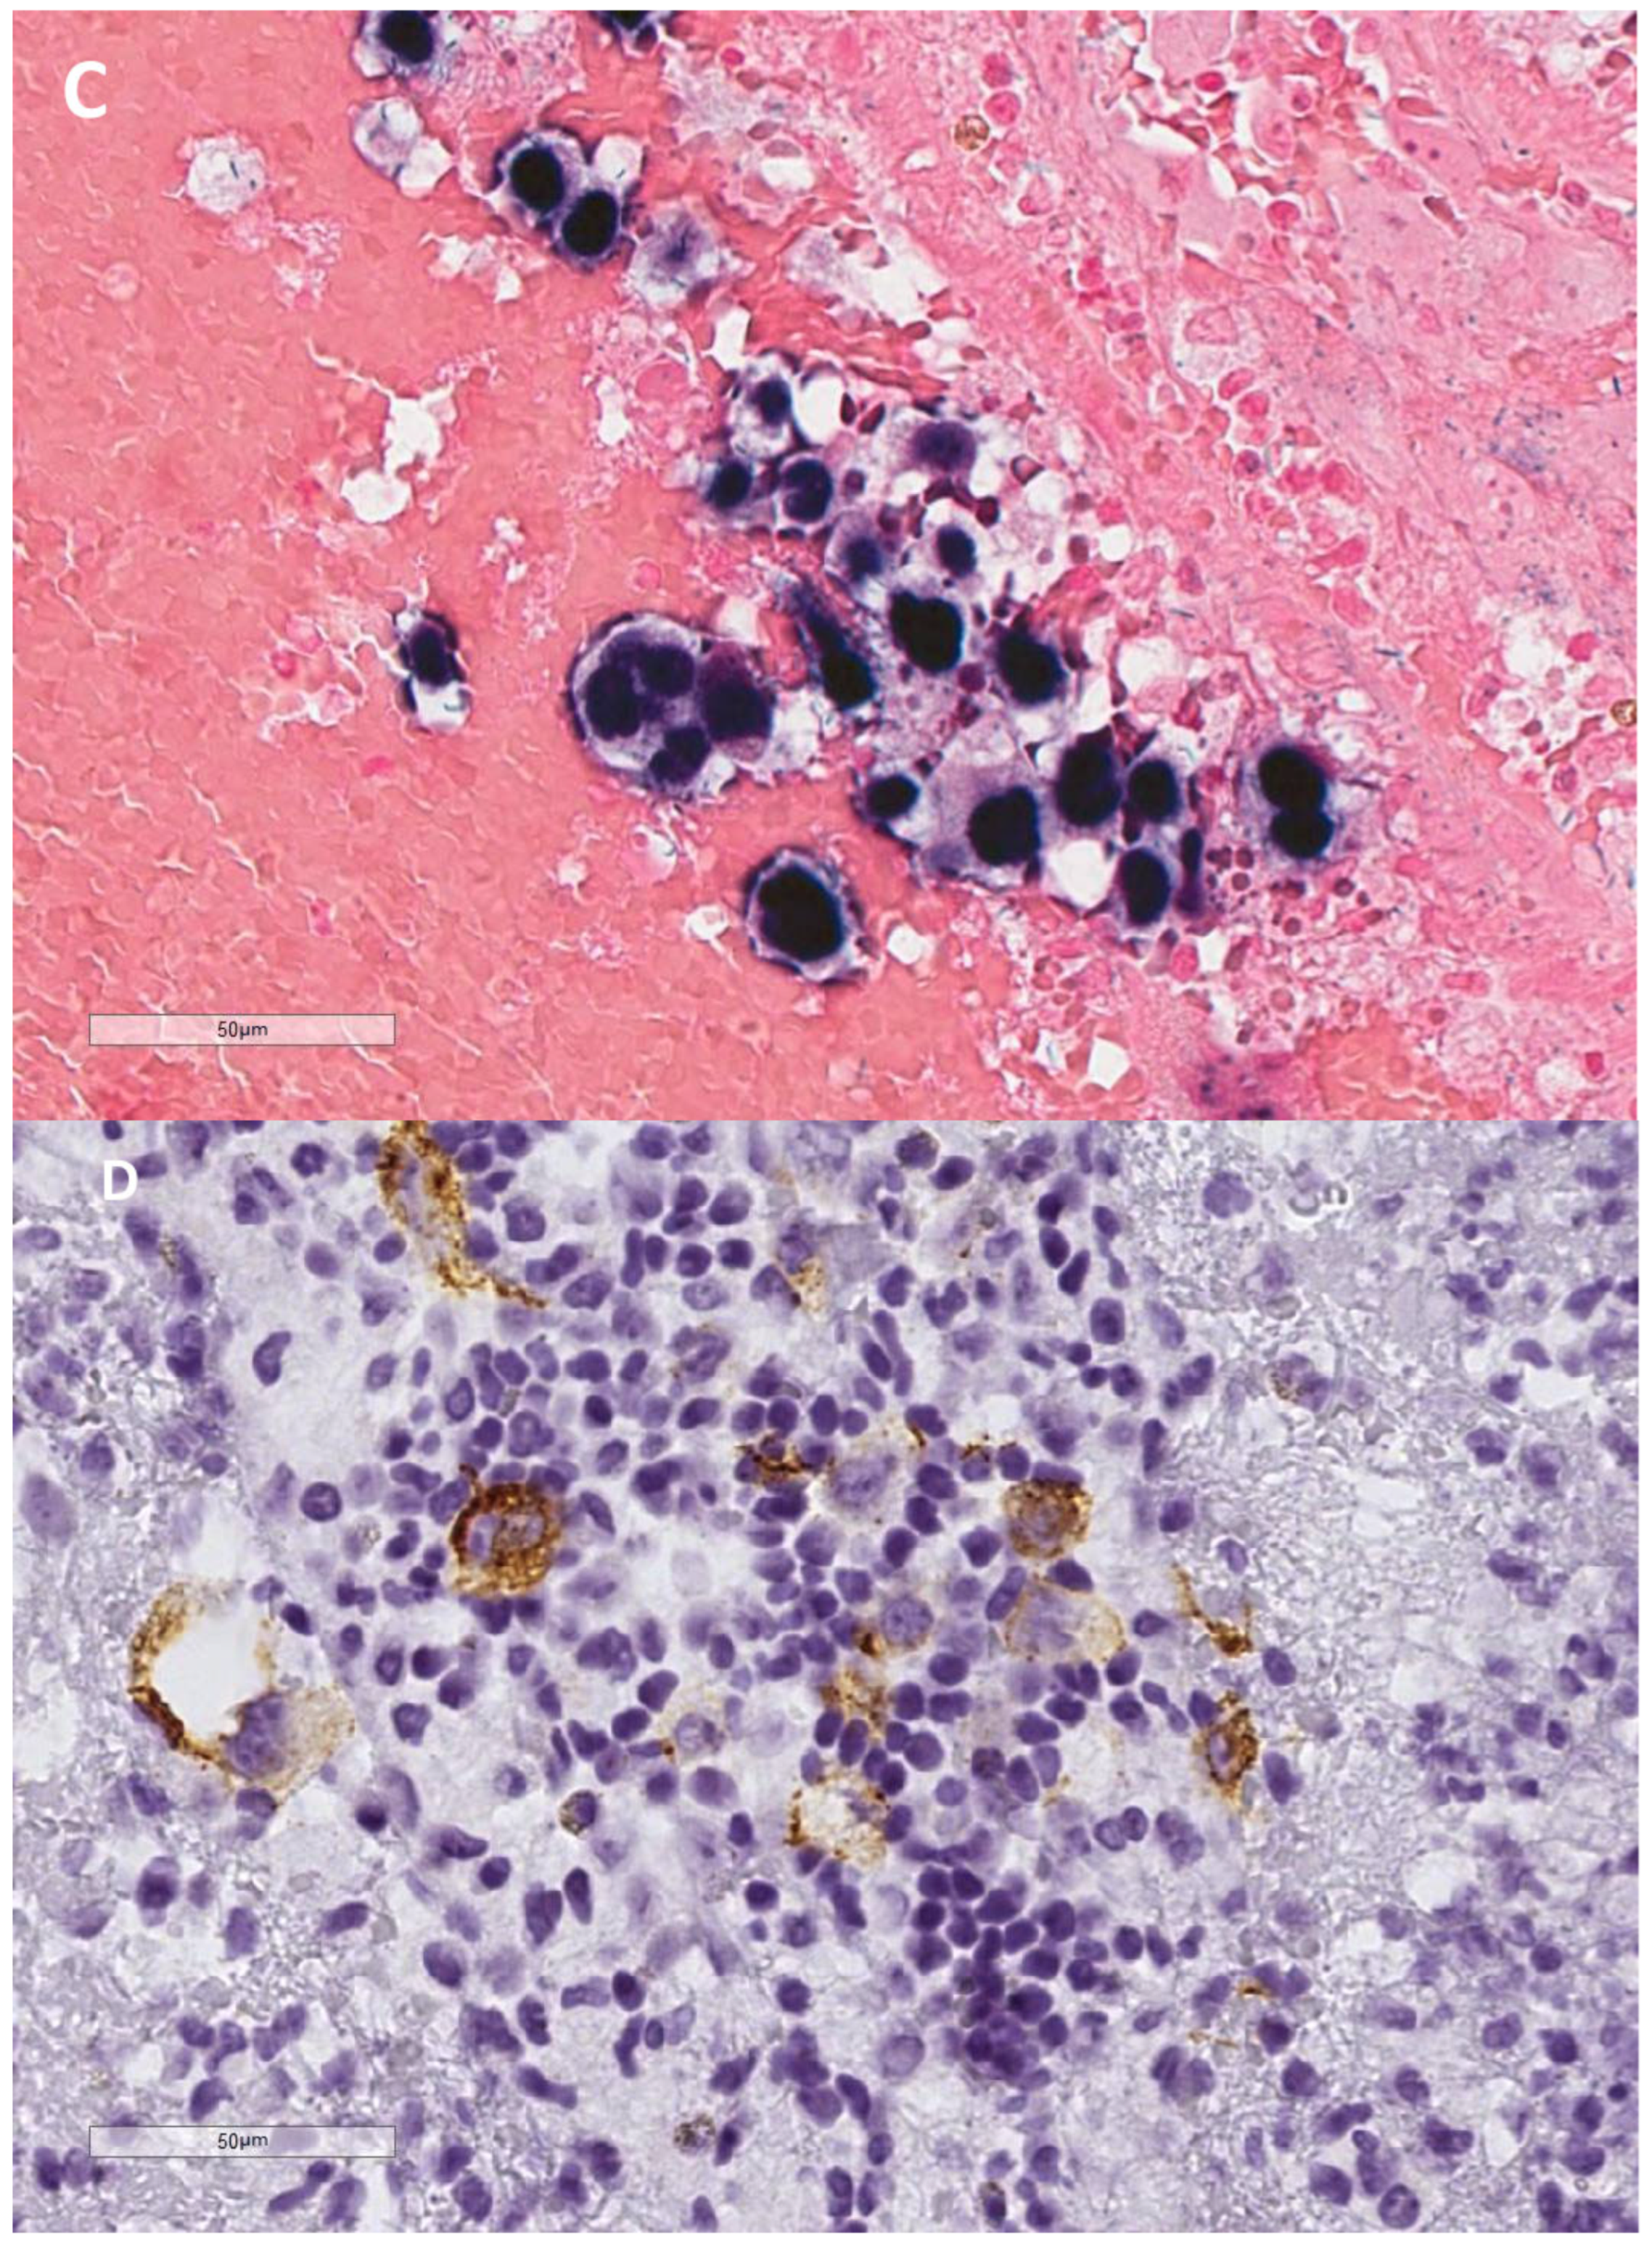

- Lajoie, V.; Lemieux, B.; Sawan, B.; Lichtensztejn, D.; Lichtensztejn, Z.; Wellinger, R.; Mai, S.; Knecht, H. LMP1 mediates multinuclearity through downregulation of shelterin proteins and formation of telomeric aggregates. Blood 2015, 125, 2101–2110. [Google Scholar] [CrossRef] [PubMed] [PubMed Central]

- Knecht, H.; Johnson, N.A.; Haliotis, T.; Lichtensztejn, D.; Mai, S. Disruption of direct 3D telomere-TRF2 interaction through two molecularly disparate mechanisms is a hallmark of primary Hodgkin and Reed-Sternberg cells. Lab. Investig. 2017, 97, 772–781. [Google Scholar] [CrossRef]

- Contu, F.; Rangel-Pozzo, A.; Trokajlo, P.; Wark, L.; Klewes, L.; Johnson, N.A.; Petrogiannis-Haliotis, T.; Gartner, J.G.; Garini, Y.; Vanni, R.; et al. Distinct 3D Structural Patterns of Lamin A/C Expression in Hodgkin and Reed-Sternberg Cells. Cancers 2018, 10, 286. [Google Scholar] [CrossRef]